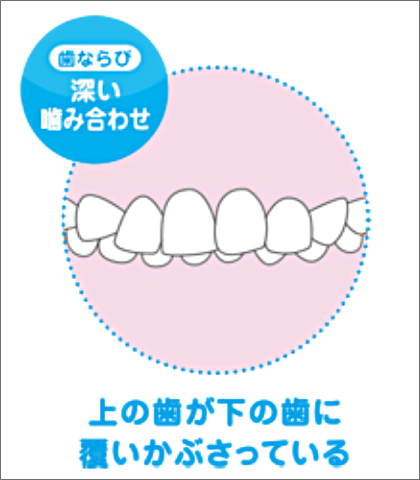

メリットは、歯ならび以外にも、噛み合わせやお口ポカン、口呼吸から鼻呼吸への改善など、お子さまを健康な体へ導くことを目的としています。プレオルソは、様々なタイプの歯ならびを改善することができます。

様々なタイプの歯ならび